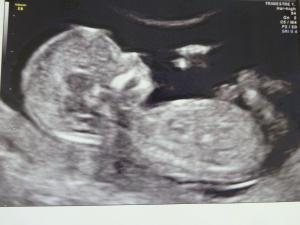

NOME: Paciocco

ALTEZZA: 7,6 cm

RESIDENTE in: Pancia di MI

SEGNI PARTICOLARI: orecchie a punta!

Vi presento ufficialmente la nostra meraviglia! La dottoressa stamattina ci ha fatto un super servizio fotografico da tutte le angolazioni. La ginecolga mi ha detto di andare in bagno a fare pipi' (e meno male perchè non riuscivo più a trattenermi!) e al ritorno...voilà, il piccolino si era girato e ci mostrava il suo profilo migliore! La dottoressa ha detto che è proprio un bimbo ubbidiente e gentile. :) Speriamo lo sia anche dopo la nascita. Abbiamo visto quindi tutto il necessario, comprese le cavità del cuore, gli emisferi cerebrali, i cristallini nell'occhio in via di formazione, la spina dorsale, lo stomaco, la minuscola vescichina (ehi questo mi fa pipi' in pancia!), le dita delle mani e dei piedi (cinque per fortuna in ogni mano) e le orecchie... a punta! Sembrava il Dr Spock di Star Trek! Ma niente di strano, la dottoressa ci ha detto che è normale che le orecchie siano cosi' perchè si stanno ancora formando.

Secondo tutte le misurazioni fatte, lo sviluppo è normalissimo e la crescita coincide perfettamente con la data presunta di concepimento. Per quanto riguarda i parametri di riferimento per lo screening della trisomia 21, non c'è alcun motivo per sospettare rischi di questo tipo. Il valore della translucenza nucale è di 1,14 mm ed è ben al di sotto del valore soglia (3 mm). Anche le ossa del nasino sono presenti, il che di solito non avviene appunto nei bambini Down.